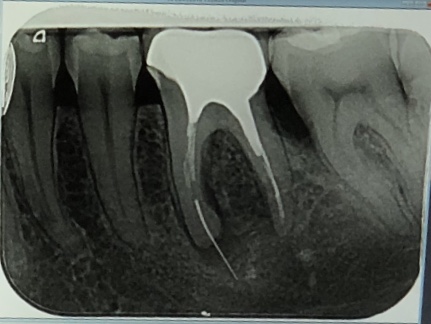

Нажмите на изображение для увеличения

Название: 97D12A67-E599-4652-992A-8CA6B4C9D0ED.jpeg

Просмотров: 46

Размер:	48.5 Кб

ID:	12724967Добрый день!

Подскажите,пожалуйста, к кому из докторов (имплплантолог/ хирург/ эндодонтист) нужно обратиться с кистой зуба (6-ка).

Образовалась из-за оставленного инструмента в канале,который на 3-4 мм вышел за верхушку корня и застрял в кости (это было приблизительно 15 лет назад)

Зуб под коронкой. Прежде был очень разрушен, в связи с этим установлены вкладки, на которые крепится коронка.

Интересует специалист с большим опытом, подойдёт любой город (не только Одесса), так как ситуация не из простых. Щека раздулась.

Хочется,чтобы доктор попытался спаси зуб и извлечь инструмент.

...выполняется операция кистэктомии с резекцией верхушки корня...дефект заполняется костнопластическим материалом...

Желательно видеть КТ этого зуба.